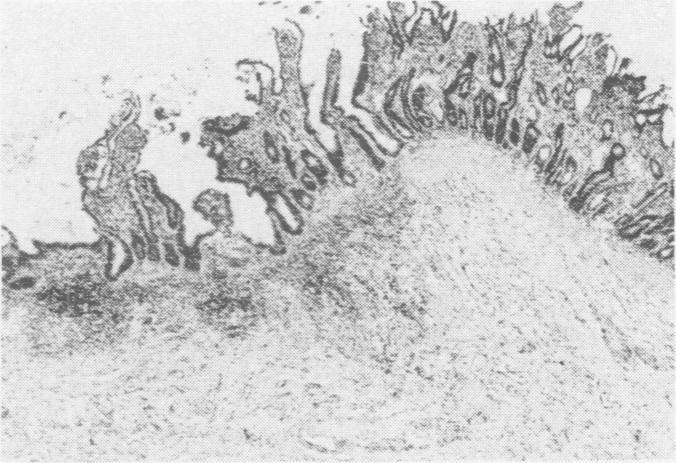

Five eight week old dogs were inoculated orally and intranasally with cell culture origin canine parvovirus. Three dogs became depressed and anorectic and developed a mild (one dog) to severe diarrhea five days postinfection. The remaining dogs had subclinical infections but developed a lymphopenia followed by a transient lymphocytosis. The ill dogs developed mild (one dog) to severe neutropenia and a moderate lymphopenia. One died nine days postinfection. Recovery was associated with cessation of viral excretion and with lymphocytosis and antibody production. Two of three dogs challenged intragastrically developed mild clinical signs and a moderate panleukopenia four to eight days postinfection. The pathological changes of the experimental disease were very similar to that of spontaneous disease. Bone marrow changes included a severe granulocytic and mild erythroid depletion. The pathogenesis of canine parvovirus infection is discussed.

五只八周龄的狗经口服和鼻内接种细胞培养来源的犬细小病毒。三只狗在感染后五天变得抑郁、厌食,并出现了轻度(一只狗)至重度腹泻。其余的狗有亚临床感染,但出现了淋巴细胞减少,随后是短暂的淋巴细胞增多。患病的狗出现了轻度(一只狗)至重度中性粒细胞减少和中度淋巴细胞减少。一只在感染后九天死亡。恢复与病毒排泄停止、淋巴细胞增多和抗体产生有关。三只经胃内攻击的狗中有两只在感染后四至八天出现了轻度临床症状和中度全血细胞减少。实验性疾病的病理变化与自发性疾病非常相似。骨髓变化包括严重的粒细胞减少和轻度的红细胞减少。本文讨论了犬细小病毒感染的发病机制。